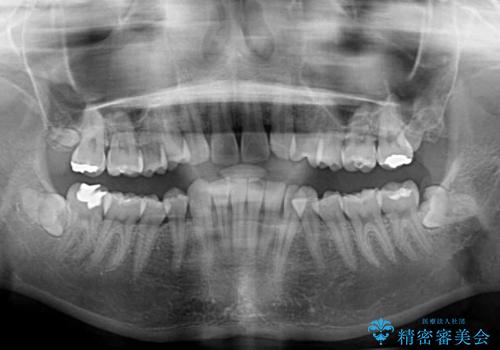

上顎前歯が2本欠損 インビザラインによる叢生の解消

- 深い咬み合わせと前歯のデコボコを気にして来院された患者様です。

上顎前歯2本が欠損しているため、妥協的なゴールを設定しインビザラインで矯正治療を行うこととしました。

上下前歯の大きさのアンバランスにより、深い咬み合わせと奥歯の咬みにくさがなかなか解決されず、治療に長期間を要することとなりました。